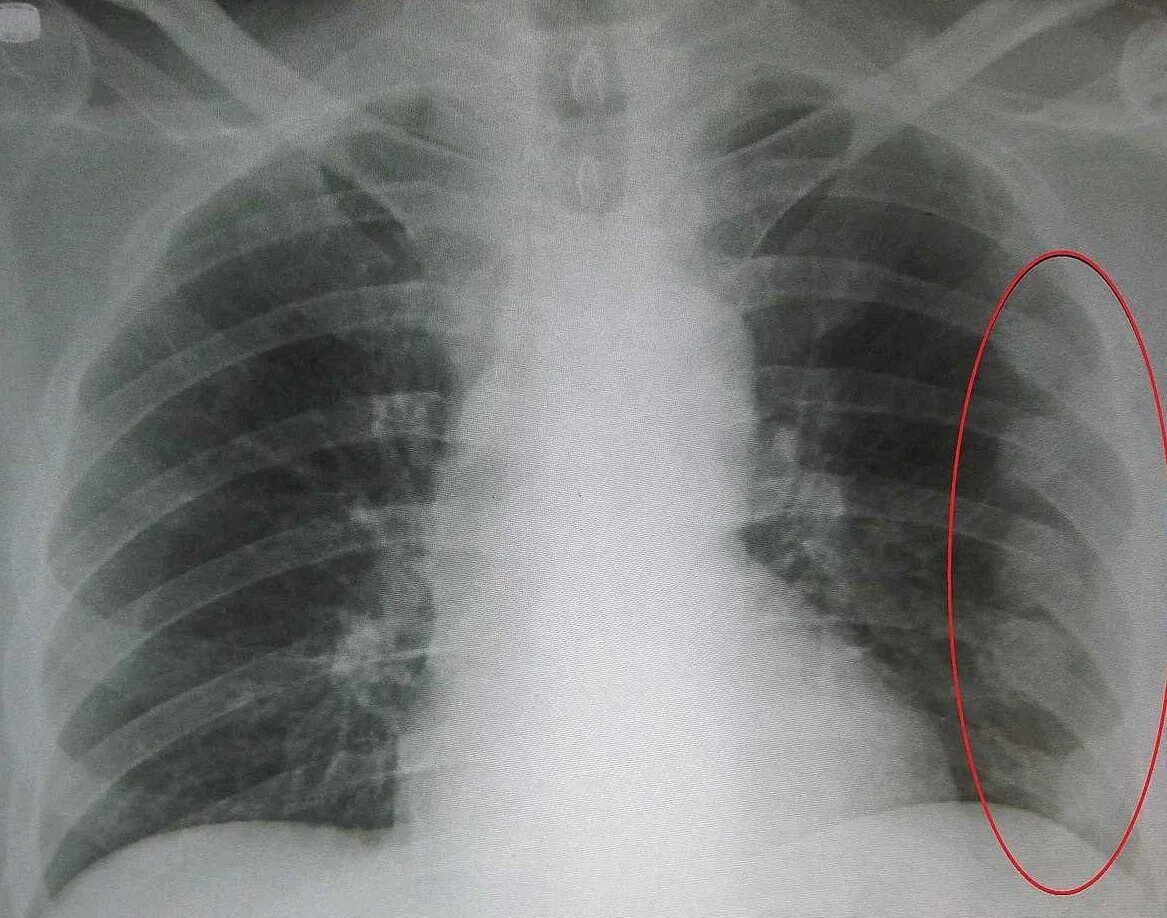

Как определить перелом ребра или ушиб